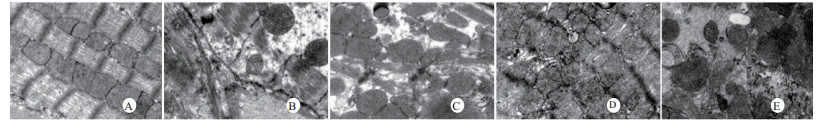

光镜下可见,假手术组肺泡大小形态均匀,结构清晰,肺泡腔内无出血和白细胞浸润;感染性休克组肺泡壁破坏严重,血管壁和肺泡间隔明显增厚;U50488H+感染性休克组大部分肺泡腔均匀一致,肺间隔略增厚,肺泡壁轻度水肿,但出血和白细胞浸润情况比感染性休克组明显减轻(图 1)。假手术组心肌细胞大小一致,排列整齐,核浆比正常,心肌细胞核呈椭圆型,胞浆均匀红染;感染性休克组心肌细胞肿胀,体积明显增大,细胞核大而异型,核内染色质固缩、边集,白细胞浸润明显增加;U50488H+感染性休克组多数心肌细胞形态相对正常,少数心肌细胞呈现脂肪变性(图 2)。假手术组肝细胞结构完整,肝小叶形态正常;感染性休克组肝细胞显著肿胀、呈空泡样和点状/小片状坏死;U50488H+感染性休克组肝细胞轻度肿胀,未见明显坏死灶、肝血窦扩张和炎性细胞浸润(图 3)。假手术组肾组织结构大致正常;感染性休克组肾小管细胞轻度水肿、空泡变性;U50488H+感染性休克组肾小管形态大致正常,间质无明显出血水肿(图 4)。

| A:假手术组,B:感染性休克组,C:U50488H+感染性休克组,D:nor-BNI+U50488H+感染性休克组,E:nor-BNI+感染性休克组 图 2 各组光镜下心肌组织病理学改变(HE×400) Fig 2 Histopathological features of myocardium(HE×400) |

扫描电镜下可见,假手术组肺泡形态完整,肺泡壁光滑;感染性休克组肺泡明显压缩畸形,肺泡隔肿胀、扭曲、隆起;U50488H+感染性休克组肺泡形态大致完整,少数肺泡壁肿胀受损(图 5)。透射电镜下可见,假手术组心肌细胞形态正常;感染性休克组心肌细胞溶解、坏死、肌纤维断裂;U50488H+感染性休克组心肌细胞大致正常,无明显坏死(图 6)。假手术组肝细胞形态正常,毛细胆管未见扩张;感染性休克组肝细胞大片坏死,毛细胆管明显扩张;U50488H+感染性休克组肝细胞形态大致正常,毛细胆管略扩张(图 7)。假手术组肾小管上皮细胞形态狭长,核卵圆形,位于基底部;感染性休克组肾小管上皮断裂,微绒毛缺失;U50488H+感染性休克组肾小管上皮细胞大致正常,微绒毛不平滑,但无明显坏死(图 8)。

| A:假手术组,B:感染性休克组,C:U50488H+感染性休克组,D:nor-BNI+U50488H+感染性休克组,E:nor-BNI+感染性休克组 图 6 心肌细胞透射电镜检查(×10 000) Fig 6 Transmission electronic microscopic photos of myocardial cell(×10 000) |

本研究还进一步观察了感染性休克大鼠重要脏器的病理学变化与超微结构。结果发现,感染性休克时,肺泡壁破坏严重,血管壁和肺泡间隔明显增厚,炎症细胞浸润较多,肺泡明显压缩畸形,肺泡隔肿胀,扭曲,隆起。该结果与潘景业等的报道一致。同时实验发现,U50488H可减轻感染性休克肺泡壁出血水肿与肺组织炎性细胞浸润,抑制肺间隔增厚。实验还观察到感染性休克大鼠心肌纤维肿胀、扭曲、断裂、溶解,并由此导致心功能障碍。U50488H亦可减轻线粒体肿胀崩解和心肌细胞溶解与坏死,可能与U50488H减轻心肌抑制有关[12],具体机制与分子通路尚需进一步实验验证。本研究还观察到感染性休克大鼠肝细胞出现肿胀、空泡样脂肪变性和点状/小片状坏死,毛细胆管明显增多、扩张;肾小管细胞轻度水肿、空泡变性,肾小管上皮细胞微绒毛缺失,细胞崩解,肾小管上皮断裂。预先给予U50488H可显著减轻感染性休克肝细胞浊肿、肝血窦扩张和炎性细胞浸润;抑制肾小管上皮细胞核变形、微绒毛坏死和间质出血水肿。nor-BNI可阻断这一效应。上述结果均提示U50488H可通过激动κ-阿片受体,改善肝脏和肾脏血流量保护感染性休克肝脏和肾脏功能,具体机制可能和细胞凋亡等相关。